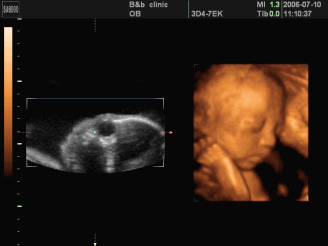

四维彩超

是备受宝爸宝妈们关注的产检项目之一

6 s! E" x0 h4 z3 t4 t四维彩超能够多方位、多角度地观察宫内胎儿的生长发育情况,对胎儿先天性体表畸形和发育异常等情况进行早期诊断筛查。

【胎儿面部畸形】如唇腭裂等;神经系统:无脑儿、脑积水、小头畸形、脊柱裂及脑脊膜膨出。$ }7 S, Z* V, O# D

【消化系统】脐部肠膨出、内脏外翻、肠道闭锁及巨结肠等。5 i. k! U/ j: z/ g1 q: F5 H

【泌尿系统】肾积水、多囊肾及巨膀胱、尿道梗阻。% P7 n* x/ k3 c

【其它畸形】短肢畸形,联体畸形,唇裂、四心腔、羊水过多、过少等。医生还可以通过四维彩超来观察胎儿的张力是否良好。' j' F, a3 p$ M) w& ~  @! M$ h

一般在孕22-28周做此项目是较佳的时间。